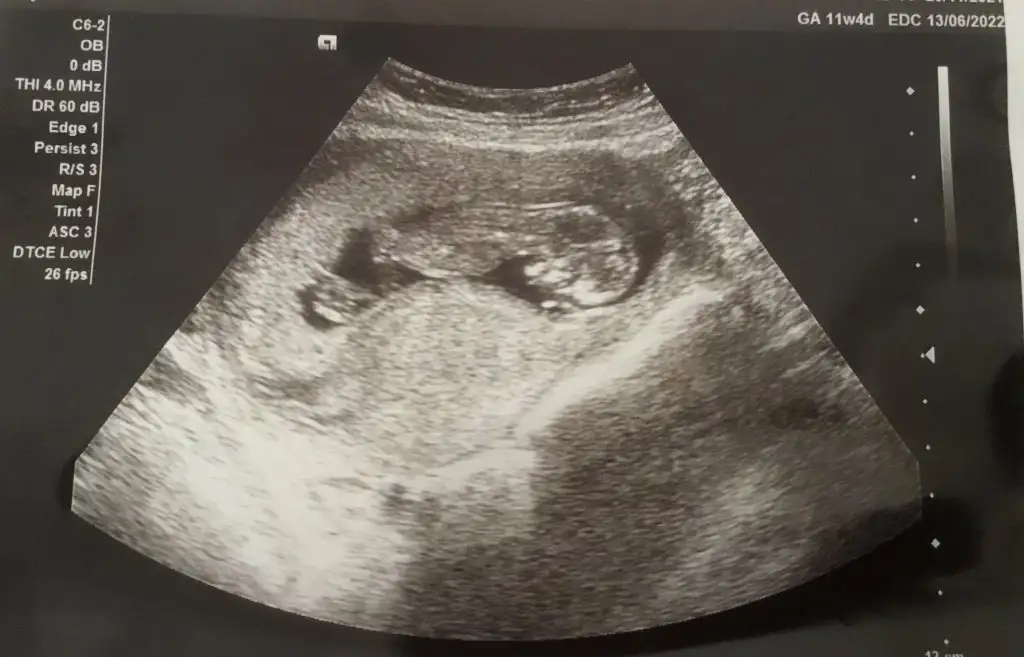

Ikra meyra Ikra meyra 11+4 teki ultrason görüntüsü, tahmininiz olur mu acaba?